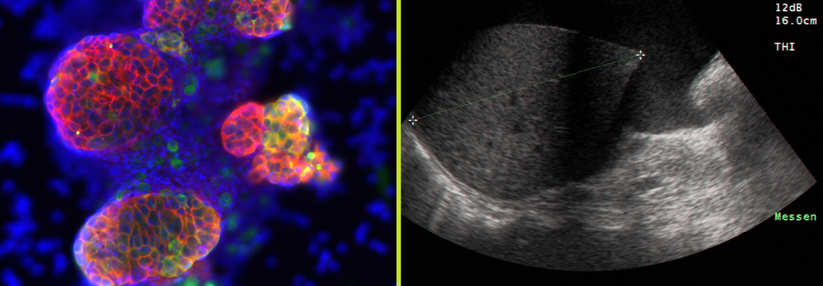

Zirrhosepatienten mit Aszites können durch Antibiotika zu 30–80 % vor einer spontanen bakteriellen Peritonitis bewahrt werden. Zirrhosepatienten mit Aszites können durch Antibiotika zu 30–80 % vor einer spontanen bakteriellen Peritonitis bewahrt werden. © wikimedia/Drahreg01; wikipedia/James Heilman